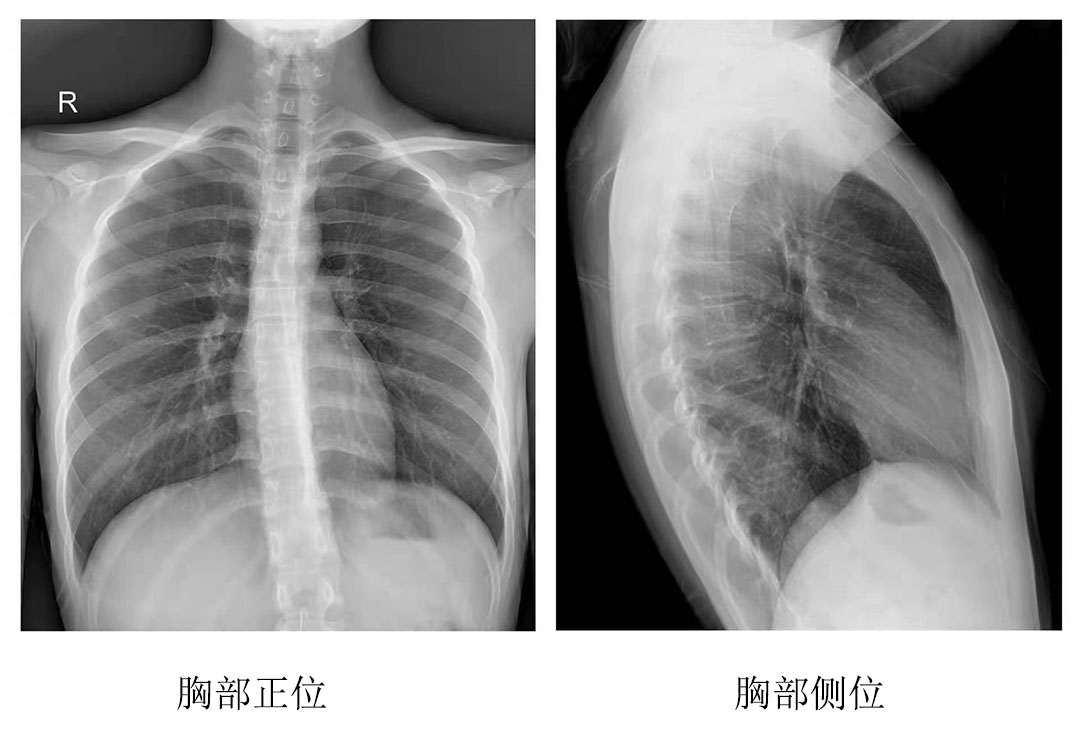

為其中一位年長的患者完成拍片工作后,操作醫(yī)師表示:今天為這位年長的患者服務時,動態(tài)平板DRF的床體升降和腳踏板360度旋轉功能很實用,上下床非常方便。不但減輕醫(yī)護人員的負擔,也縮短了患者的檢查時間,拍出來的圖像很清晰,對拍片成果很滿意。